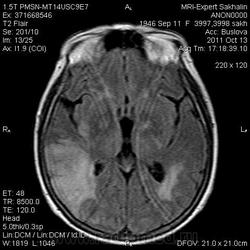

Ишемический инфаркт

Вот, Сергей Николаевич, я тоже указала, что НМК по ишемическому справа в СМА

ОНМК по ишемическому типу в бассейне правой СМА. Судя по очагам накопления в коре, подострое.

Последствия ОНМК с геморрагическим пропитыванием справа. Кистозно-атрофические изменения в левой гемисфере мозжечка (последствия ОНМК ). Множественные очаги сливного характера вещества головного мозга ( поля лейкоариоза)

Писал писал и куда-то все пропало, в общем, это не последствия инфаркта в бассейне сма.

Да хотела еще добавить возможно у пациента еще были лакунарные инсульты. В области базальных ядер( слева ) определяются кисты, окруженные глиозом. И на предпоследнем изображение в правой гемисфере мозжечка по- моему и также есть нмк.

Гглиоз, сосудистые очаги, лейкоареоз - это все при ДЭП, этим и обусловлена деменция.

С уважением, С.Н. Нагорный

Да наверное все это можно одним словом сказать дэп (хнмк). Но для невролога лучше наверное стоит дать полною описательную картину. Они как правило редко снимки смотрят, что чем более подробное описание, тем более понятна им будет картина.

Танюша, все указала-и лакунаные постишемические кисты, и кистозно-глиозные левой гемисферы мозжечка.Правая , вроде бы, не задействована в процессе.